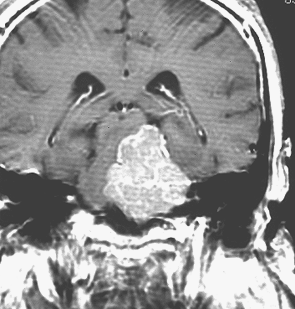

最も見やすいのが,ガドリニウム造影剤を注射して撮影するものです。一般的に髄膜腫は造影剤で白く映し出されます。この腫瘍は左脳側にあります。MRIの軸面という輪切りの写真では左右が逆になりますから注意してください。脳を下から見た図になっています。MRIはいろいろな方向から腫瘍を見ることができますが,右は冠状断という正面から見た図です。よく見ると腫瘍の上と下のはじっこに線状に糸を引いたように造影される部分があります。これをテールサイン(しっぽのサイン)といいます。腫瘍が硬膜に沿って延びている可能性があることを示しています。